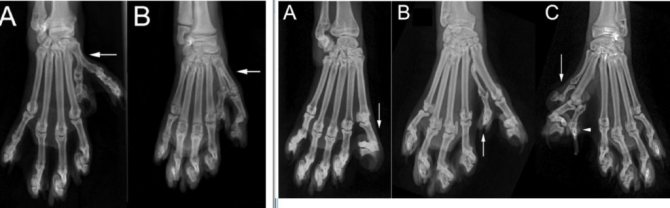

В научной литературе термин «полидактилия» («поли» — «много», «дактил» — «палец») часто обозначает наличие лишних пальцев. Существует две формы полидактилии: преаксиальная и постаксиальная. Под «аксиальной» подразумевается расположение относительно оси складывания конечностей эмбриона в матке. «Большой палец» расположен до этой оси (преаксиально), а «мизинец» — по другую ее сторону, т.е. постаксиально. У людей обычно встречается постаксиальная полидактилия, т.е. появление лишнего мизинца, тогда как у кошек это, как правило, преаксиальная полидактилия с лишними пальцами со стороны большого пальца. Форма полидактилии, наиболее часто наблюдаемая у кошек, — это проявление простого аутосомно-доминантного признака. Он не влияет отрицательно на здоровье животных и не связан с другими аномалиями развития.

Долгие годы многократно повторялось ложное заключение, что полидактилия является племенным дефектом, который влечет за собой экстремальные формы выражения и серьезные заболевания у мейн-кунов. Но ничто другое не может быть так далеко от истины — как было подтверждено научными исследованиями и общими наблюдениями в течение десятилетий. Д-р Лесли Лайонс из Калифорнийского университета (University of California, Davis) в течение нескольких лет работала с заводчиками мейн-кунов, собирая образцы ДНК для выявления гена полидактилии. Ее заключение, вкупе с рядом других исследований, звучит как: ген полидактилии (Pd) абсолютно безопасен даже в гомозиготном состоянии и не имеет ничего общего с геном радиальной гипоплазии (Rh). Также эти образцы ДНК полидактильных мейн-кунов были использованы в масштабном исследовании полидактилии у кошачьих, проводимом в 2007 году учеными Laura A. Lettice, Alison E. Hill, Paul S. Devenney и Robert E. Hill с кафедры генетики человека (MRC — Human Genetics Unit) медицинского центра Western General Hospital в Эдинбурге (Великобритания). Данное исследование было попыткой расширить знания о существующих генах, выражающихся в форме полидактилии у различных видов, включая человека, мышей и кошек. Исследование образцов ДНК кошачьих выявило 3 мутации гена полидактилии (Pd) — схожих, но имеющих слегка разное выражение. Все три мутации являются неопасными выражениями гена Pd. Исследователи пришли к заключению, что: «Анализ генетики полидактильных кошек выявил три новых мутации, связанных с преаксиальной полидактилией. Как установлено и для людей и мышей, мутации кошки лежат в генном регуляторе ZRS, что предполагает, что природа преаксиальной полидактилии кошек идентична другим млекопитающим. Поскольку эти мутации отражаются в фенотипе конечностей человека без каких-либо других выявленных физиологических дефектов, мы утверждаем, что этот тип полидактилии не влечет за собой вредоносного влияния на здоровье кошки». Информация о разведении полидактильных мейн-кунов может быть получена от опытных заводчиков, использующих их в своих племенных программах в течение нескольких лет. Они фиксировали результаты вязок полидактов на неполидактов, полидактов на полидактов и гомозиготных полидактов на неполидактов. Данные от этих заводчиков демонстрируют отсутствие отрицательных результатов при вязке двух полидактильных животных. Предлагается делать вязку полидакта и неполидакта, чтобы проследить генетику родителей и знать, кто и как передает ген полидактилии. Чтобы получить полидактильное потомство, один из родителей должен быть полидактом. Статистика показывает, что в среднем в таких пометах рождается 55.7% полидактильных котят. Отдельные пометы демонстрируют индивидуальную раскладку, и указанный процент является средним по данным многих пометов. Заводчики фиксировали отсутствие полидактильных котят в пометах, наличие одного, двух, трех и т.д. Это случайный выбор, который сравним с соотношением девочек и мальчиков в помете, когда шансы у каждого котенка примерно 50/50. В случае вязки полидакта на полидакта оценочное количество поли-котят в помете будет составлять 75%. А если один из родителей является гомозиготным полидактом, то весь помет будет полидактильным. Неоспоримым фактом остается то, что этот ген имеет различную выраженность в потомстве вне зависимости от комбинации пальцев родителей. Он не является летальным и выражает себя по-разному даже в гомозиготной форме, что нехарактерно для других доминантных генов. Поскольку ген полидактилии может выражаться по-разному, было разработано руководство для определения конфигурации «больших», обычных и рудиментарных пальцев.

Обычно у кошки на передних лапах по пять пальцев и по четыре – на задних. У полидактильных кошек, как правило, на одной лапе на 1-2 пальца больше, чем у обычных их представителей. Кроме того и конфигурация этих пальцев бывает различной. Ген полидактилии проявляет себя в 40-50% случаев и не зависит от пола животного.

Некоторые полидактильные кошки являются обладателями так называемой «лапы-варежки». Такая лапа образована «лишними» пальцами, прикрепленными во внутренней стороне лапы. Многие из кошек умеют этими пальцами двигать точно так же как и люди. Такие представители кошачьего мира с легкостью могут открывать любые двери. Кошки, у которых пальцы размещены в одну линию, назвали кошками с «лапами-снегоступами» или «лапами-блинами». Внешне их лапы похожи на рысьи. Благодаря такому строению эти кошки легко перемещаются по глубокому снегу.